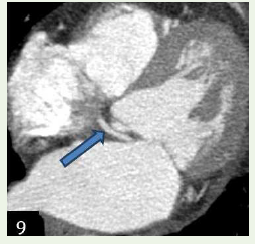

Case 4: A 68-year-old female with c/o chest pain, case of hypercholesterolemia and diabetes and concentric le ventricular hypertrophy in echocardiogram, demonstrated an anomalous origin of Left circumflex artery from the right coronary sinus with retro- aortic course.

Figure 9:Maximum intensity projection reconstruction and 3D volume

rendered reformation shows an anomalous origin of Left circumflex artery

from the right coronary sinus with retro-aortic course.